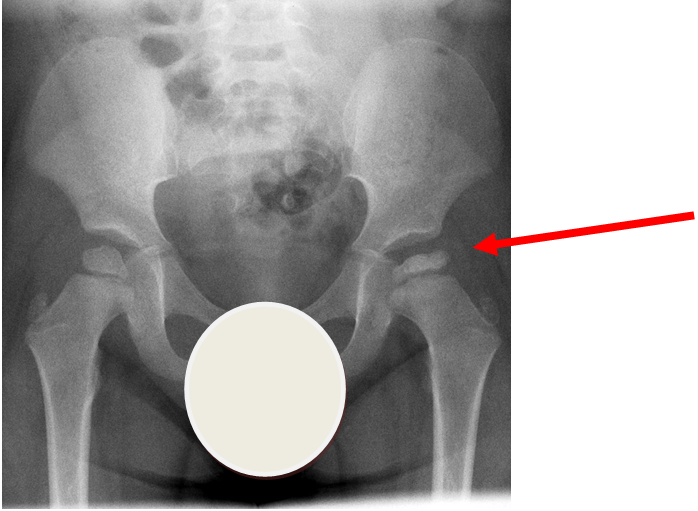

3.Perthes Disease

Case courtesy of A.Prof Frank Gaillard, Radiopaedia.org. From the case rID: 7980

Perthes disease or avascular necrosis of the capital femoral epiphysis is more common in boys than girls (approximately 4:1). Onset is usually over weeks and typically between the ages of 3-9 years old. 15% are bilateral. X-ray of the pelvis shows flattening of the femoral head with joint space widening. X-ray changes may be absent in early disease.

The child is systemically well with no other joint involvement and no evidence of joint inflammation.

Investigation

- X-ray - AP pelvis